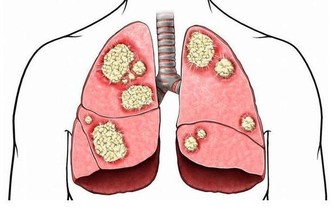

一定量的內臟脂肪其實是人體必需的,

因為內臟脂肪圍繞著人的臟器,對人的內臟起著支撐、穩定和保護的作用。

然而,當內臟脂肪堆積過多時,一方面就會形成水

桶腰、將軍肚等造成身材不美觀的問題;另一方面,內臟長期堆積過多脂肪會影響消化功能,

導致內分泌紊亂,還增加了患高血脂、高血壓、脂肪肝等疾病的機會,